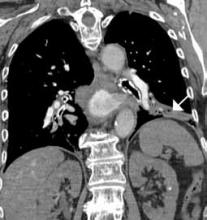

Figure 1. Coronal (A) and axial (B) contrast-enhanced computed tomography angiography scans reveal pulmonary embolism (white arrows)..

CTA has long been the standard technique for evaluating PE. In addition to reported sensitivities of 96% to 100% and specificities of 97% to 98% with multislice detectors,2 CTA also provides information on disease severity, such as clot burden, evidence of right heart strain, and the presence of pulmonary infarct (Figure 1). It also can reveal alternative etiology and diagnosis in negative cases (Figure 2).